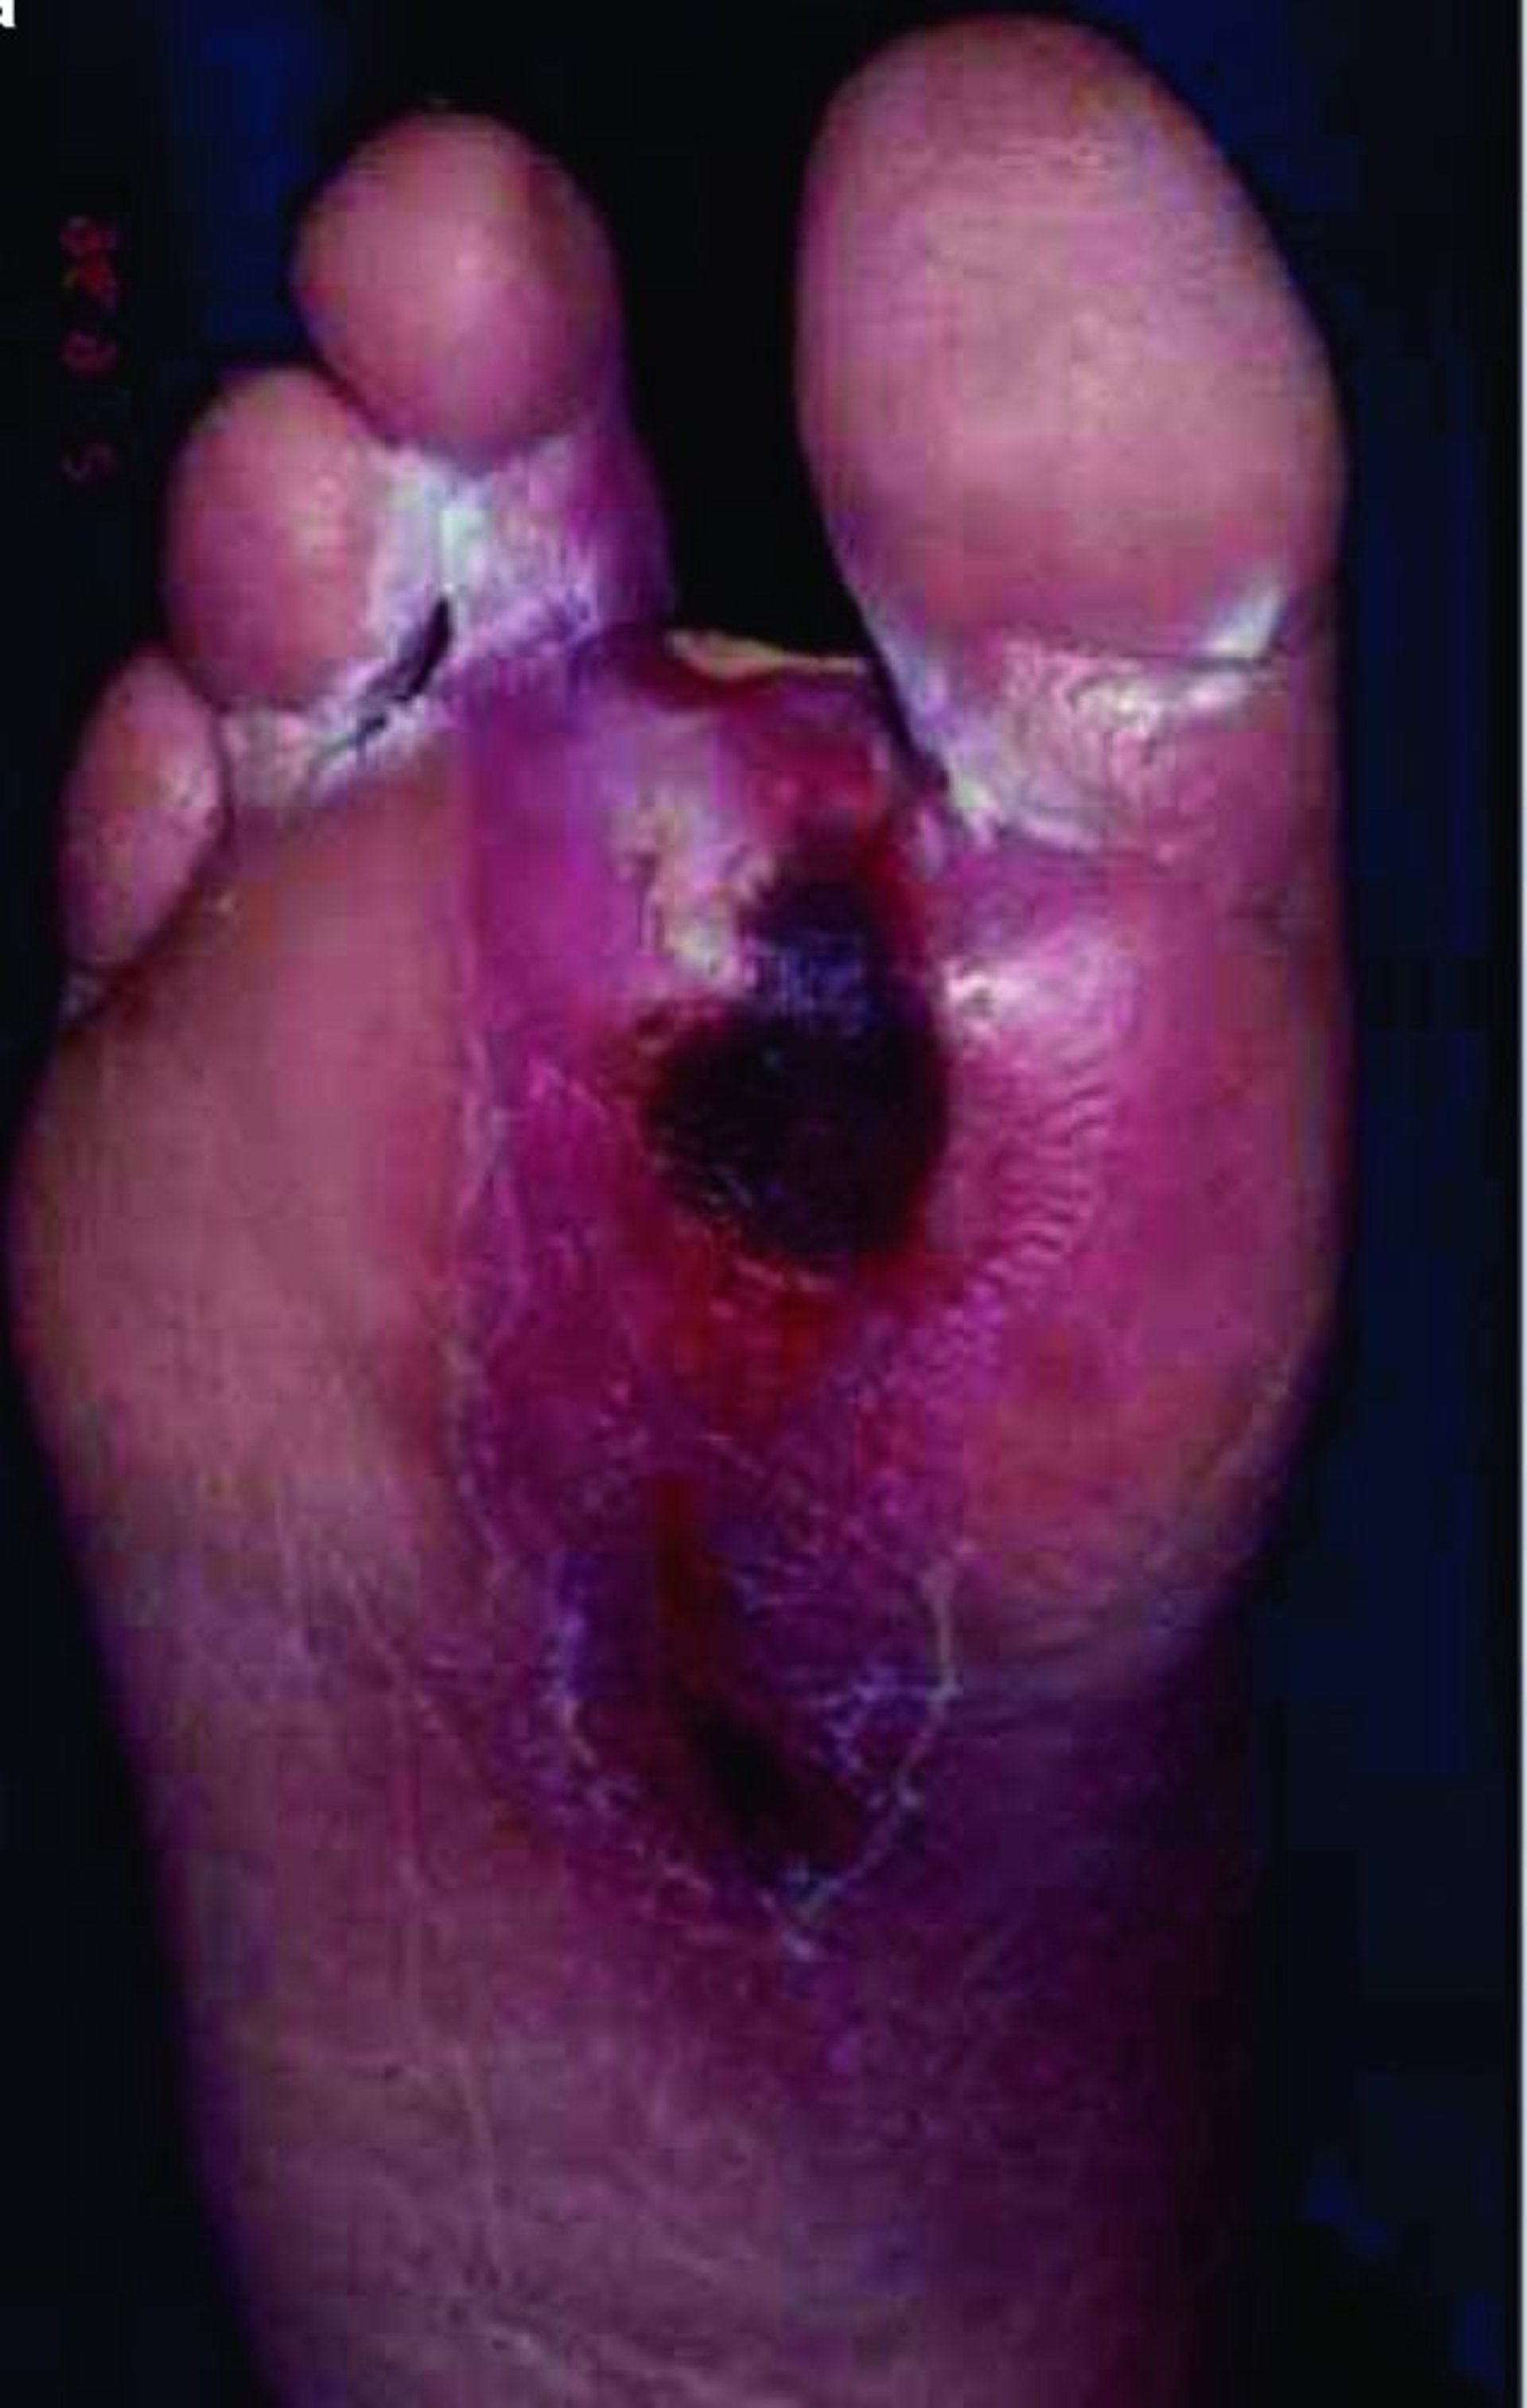

Ulcère du pied

Un patient diabétique développe souvent une maladie microvasculaire qui peut altérer la cicatrisation, de sorte que même des plaies mineures peuvent évoluer vers des ulcères plus profonds qui s'infectent facilement, surtout au niveau des membres inférieurs.